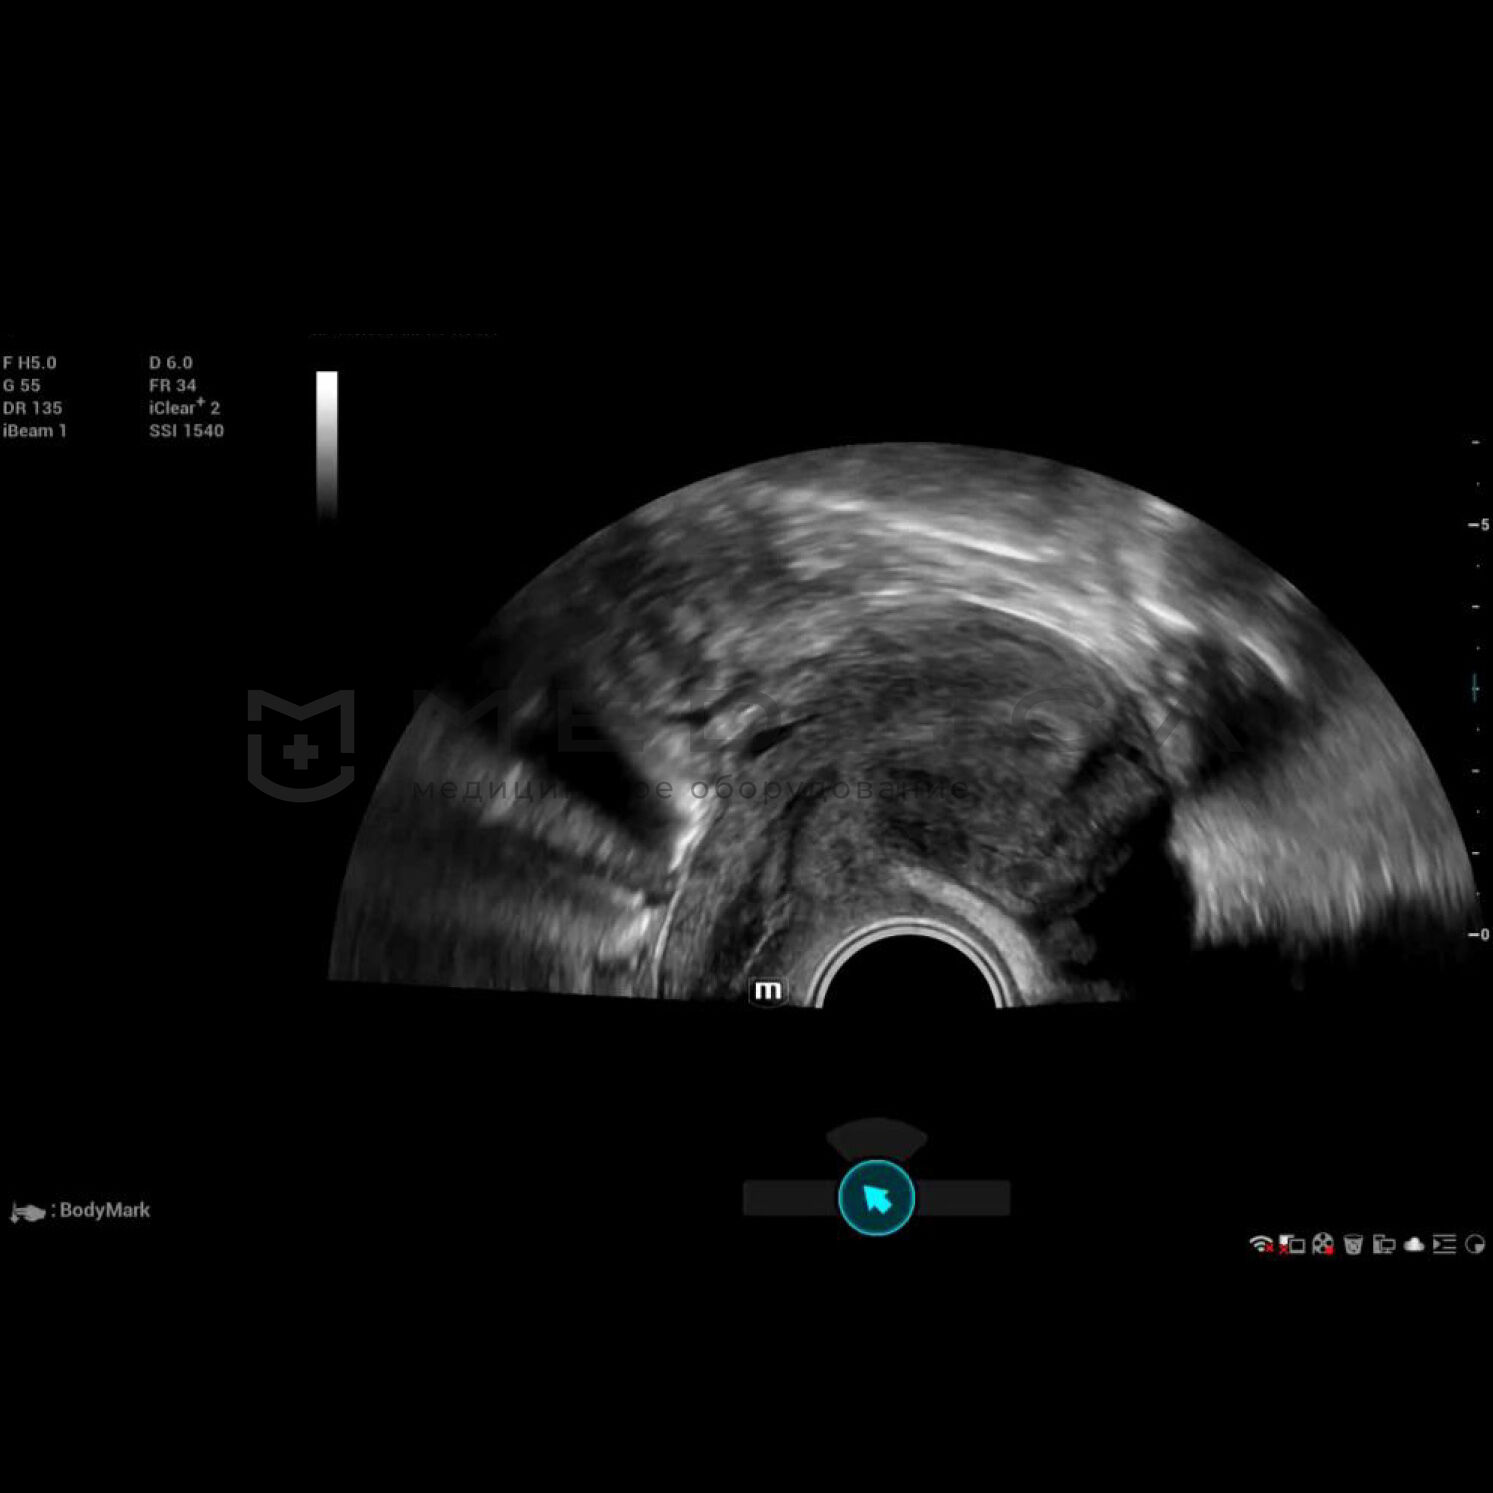

Полноценное интеллектуальное решение для диагностики матки, для легкой и быстрой оценки эндометрия

- Автоматическое распознавание матки

- Автоматическая подстройка зоны интереса и положения до оптимального

- Автоматический объемный рендеринг эндометрия

Место Smart Scene в технологии full-stack smartness